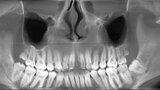

Ryc. 3_Zęby 11 i 21 po ekstrakcji.